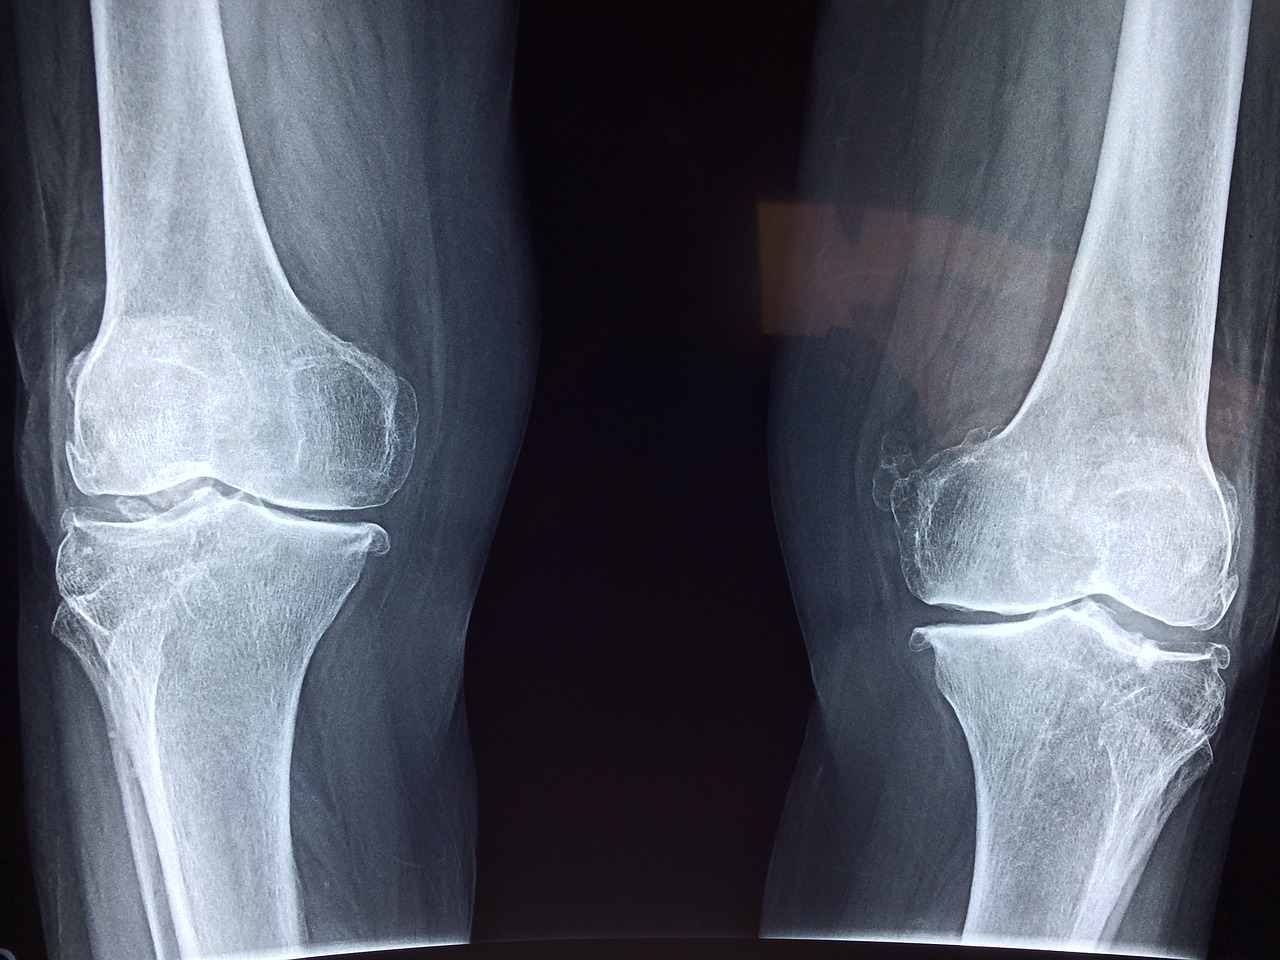

Może pomóc w usuwaniu kamieni z dróg moczowych i stawów oraz łagodzić ból stawów i mięśni. Skrzyp polny jest również skuteczny w łagodzeniu kaszlu, flegmy i chorób skóry oraz uspokajaniu układu nerwowego. Pomaga także w przypadkach takich jak stwardnienie naczyń krwionośnych, oczyszczanie układu naczyniowego, zatrzymywanie krwawień z nosa i ran, leczenie hemoroidów, gruźlicy, bólu gardła, oczyszczanie krwi oraz w łagodzeniu bolesnych stanów zapalnych.

Skrzyp polny jest również korzystny dla zdrowia naczyń krwionośnych. Poprawia elastyczność ścian naczyń, zapobiega stwardnieniu i poprawia przepływ krwi. Pomaga również w usuwaniu szkodliwych substancji z układu naczyniowego, co korzystnie wpływa nie tylko na nerki, ale również na wątrobę i inne narządy w organizmie. Skrzyp polny może również pomóc w przypadku chorób związanych z układem naczyniowym i krążeniowym, takich jak dna moczanowa, reumatyzm, żylaki czy stany zapalne. Ponadto skrzyp polny może łagodzić ból gardła.

Herbata z rośliny skrzypu polnego skutecznie eliminuje kamienie nerkowe i moczowe. Dodatkowo, korzystnie wpływa na zdrowie kości oraz pomaga w leczeniu osteoporozy. Skrzyp zawiera także olejki eteryczne, które likwidują pleśń i bakterie.

Receptura na złagodzenie bólu pleców, stawów i kości

Wlej alkohol do szklanki, a następnie wciskaj skrzyp polny jak najmocniej, jak to tylko możliwe. Zamknij szklankę, umieść ją na parapecie i pozostaw do zaparzenia przez około 2 tygodnie. Następnie namocz grubą gazę w roztworze i aplikuj ją na bolące miejsce wieczorem lub przed snem (można stosować na różne dolegliwości, np. na bóle pięt lub kolana).

Przykryj miejsce opatrunkiem i owiń, aby nie brudzić pościeli. Pozostaw na całą noc, szczególnie upewniając się, że miejsce nie ostygnęło. Powtarzaj przez 3 noce, aż ból ustąpi. W moim przypadku, już po pierwszej nocy odczułam ulgę, a po trzeciej nocy ból całkowicie zniknął.